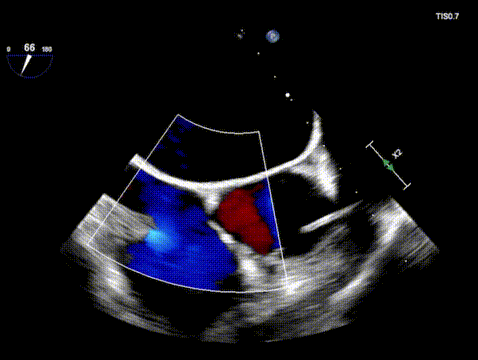

术前超声

术后超声